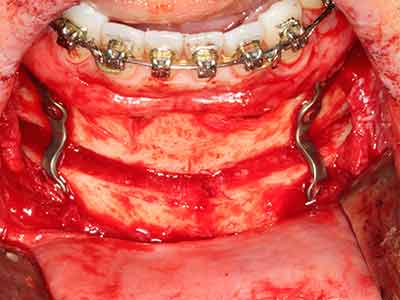

Bone tissue is not simply a mineral structure but also contains a substantial proportion of collagen fibres. This means it not only has good compressive strength but also a degree of flexibility, which can be taken advantage of when performing bone augmentations. In the classical expansion procedure using bone splitting, the atrophied alveolar ridge is split longitudinally and carefully expanded after reaching an adequate osteotomy depth (Fig. 13-16), ideally without substantial removal of the periosteum (Brugnami, Caiazzo et al. 2014, Stricker, Fleiner et al. 2014). Screw and plate systems with increasing expansion distance have proven effective in separating the two bone lamellae while remaining below the fracture threshold. In general, residual bone widths of at least 3–4 mm are required (Chiapasco, Zaniboni et al. 2006) to guarantee adequate flexibility and sufficient bone coverage of the future implants. If necessary, a vertical relief osteotomy on one or both sides can improve flexibility. A combination with additional augmentation techniques, particularly on the buccal side, has been described as an alternative to the classical technique.